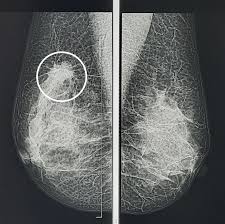

- Инструментальные исследования. Обязательными методами являются УЗИ молочных желез (для женщин до 40 лет) и маммография (для женщин старше 40 лет). Эти исследования помогают оценить структуру тканей и исключить наличие кист, фиброаденом или злокачественных опухолей, что особенно важно перед планированием любого вмешательства.